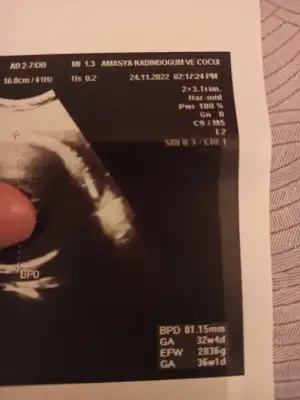

Gözün Aydın canım inşallah bir an önce bebeğinle kavuşup evinize geçersiniz sağlıkla büyüsünSelam kızlar, bugün 37+5ken sezeryanla geldi minik kızım 2880 Gr,49 santimmis, suyum tamamen bitmiş ilginç bir şekilde ,bebeğimin de nefes alış verişi biraz hızlı imiş , doktor biraz rahatlasın diye kuvoze almış , benim uyuşuklugum geçince yanına ineceğim görmek için , ins çabuk toparlar kavuşuruzspinal anestezi ile oldu doğum anı bence çok rahattı bebeğim cikisina şahit olmak çok güzel sesini de duydum orda